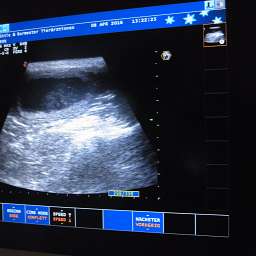

8.4.2016, 30.Tag: Heute ist ein großer Tag. Nicht nur für unsere kleine Mami Adele. Auch für uns und einige Menschen, die ihr kleines Wunder heiß ersehnen. Der Ultraschalltemin ist heute um 11.00Uhr. Hoffentlich hat Adele genug innere Ruhe und Ausgeglichenheit, um dem Stress adäquat begegnen zu können. Drückt bitte alle die Daumen. Unsicherheit scheint manchmal mein 2.Vorname zu sein...

18.00Uhr: Es ist vollbracht: "Lieber Nacho, wir dürfen Dir gratulieren. Du wirst Papa."

Mit pochendem Herzen durften wir 4 pochende Herzen unter Adeles pochendem Herzen sehen. Es ist immer wieder ein besonderer Moment. Das Wunder des Lebens nimmt seinen Lauf. Also, Ihr dürft Euch freuen: es sind mindestens 4 kleine Wunder unterwegs. Sucht Euch doch schon mal eins aus:

Adeles Gewicht aktuell 6,25Kilo.